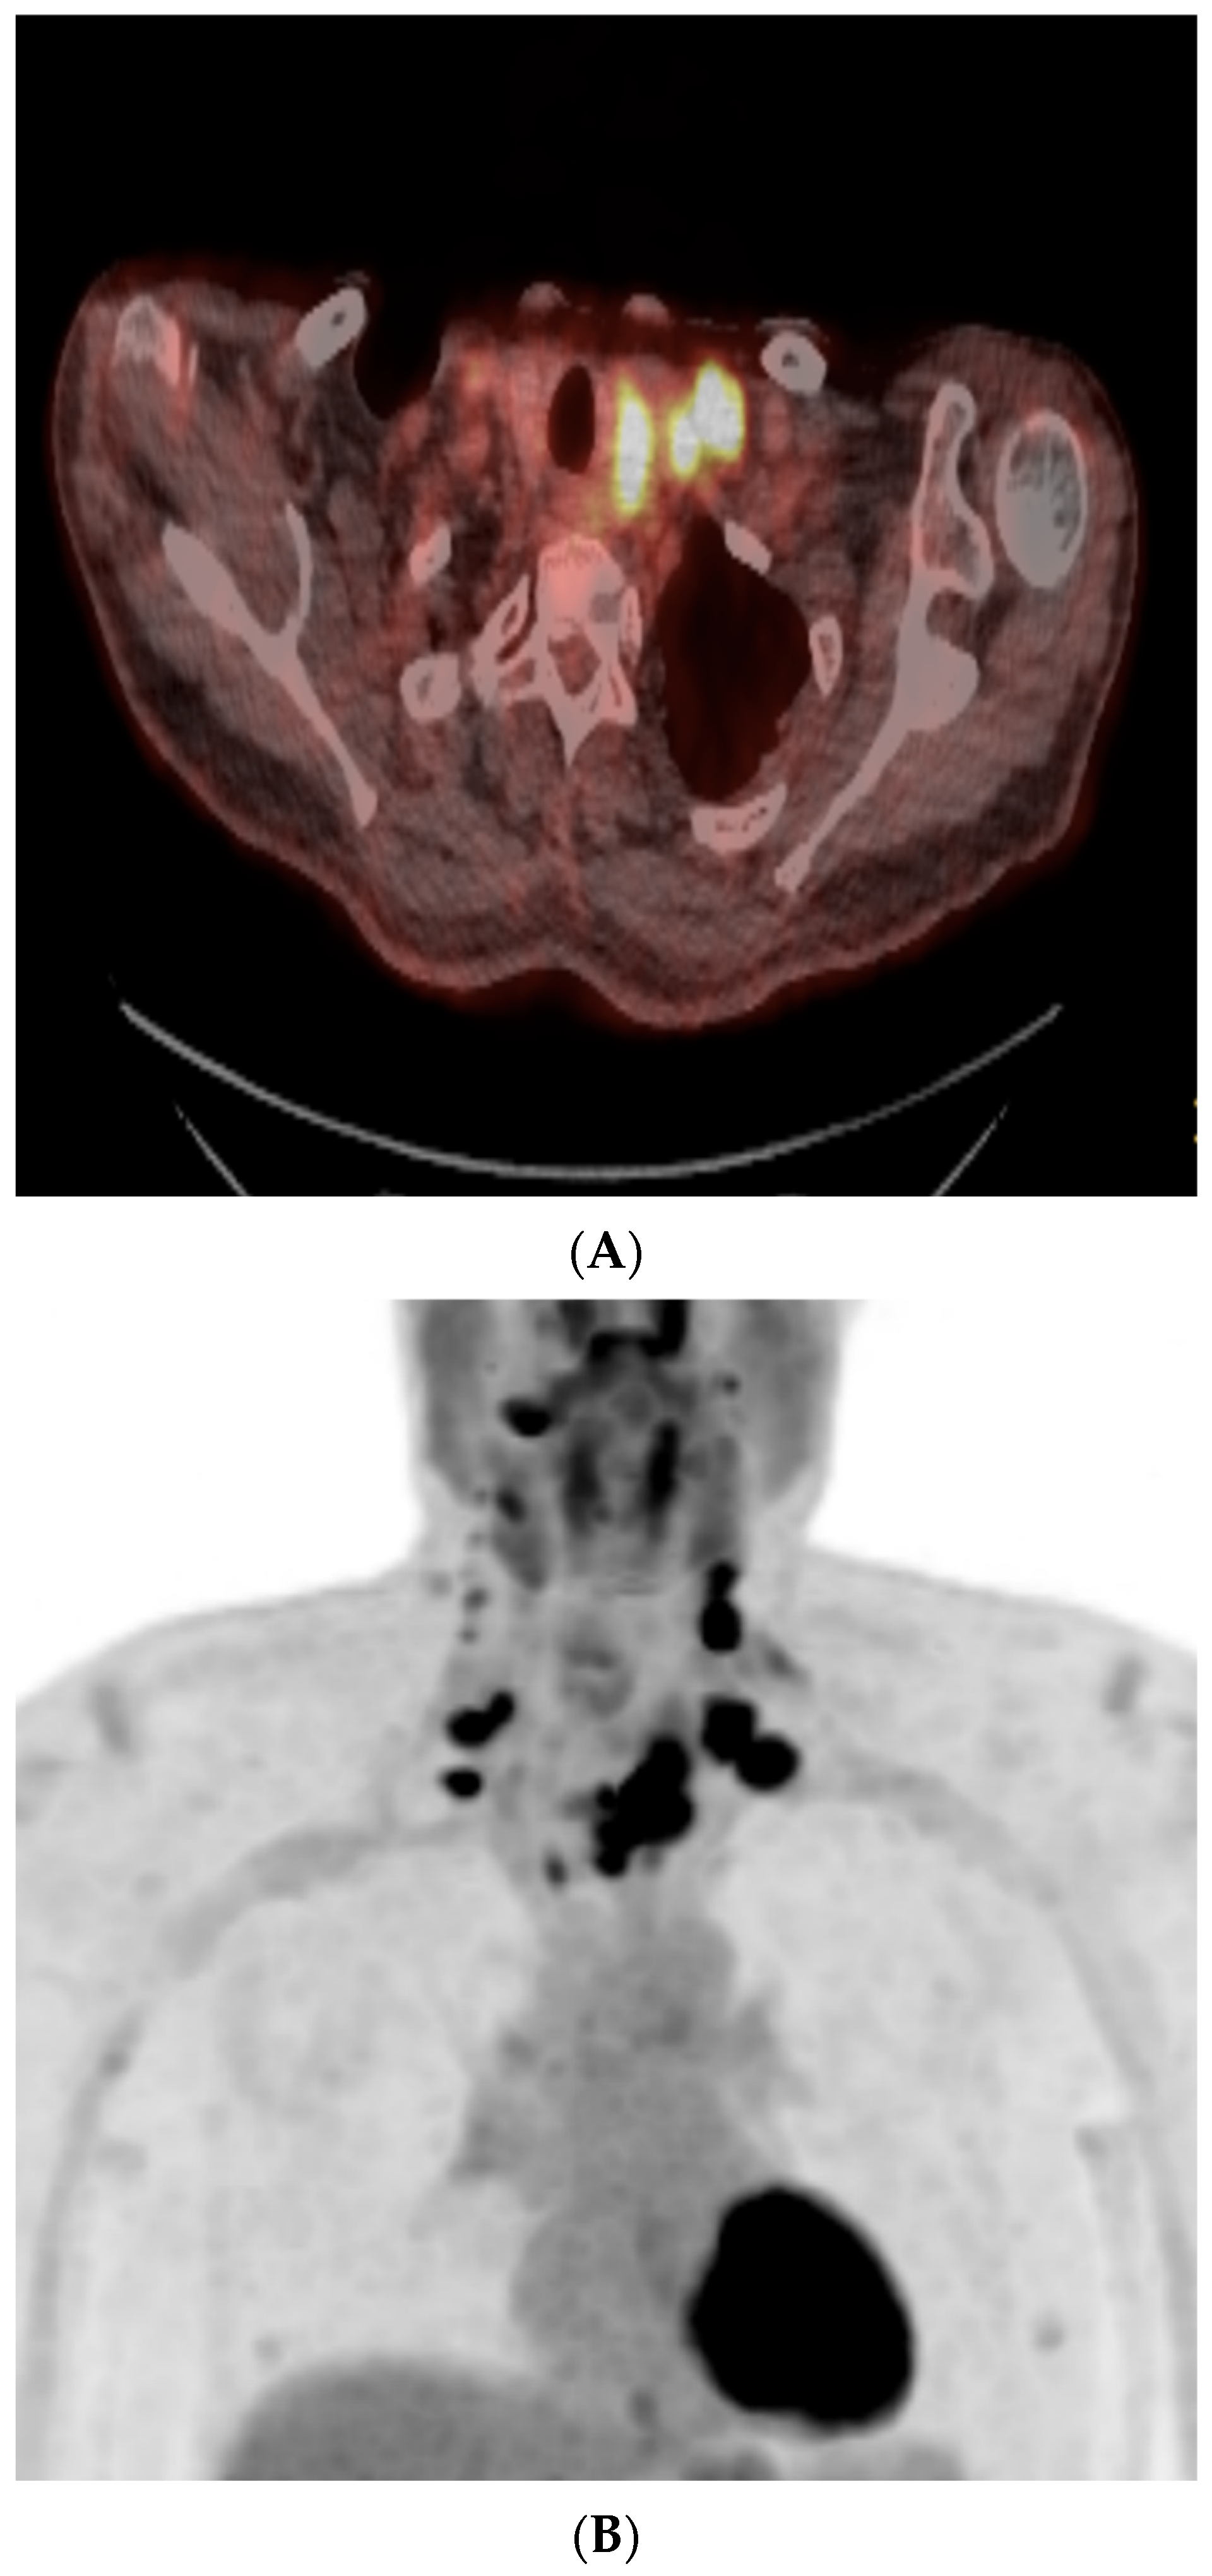

As outlined by the accompanying patient testimony, a 65-year-old gentleman presented with a 6-week history of dysphagia. Computed tomography (CT) imaging of the thorax, abdomen, and pelvis, and magnetic resonance imaging (MRI) of the neck revealed a 7.2 centimeter (cm) mass centered in the left lobe of the thyroid. The mass involved the cervical esophagus and posterior tracheal wall, leading to moderate cervical tracheal airway narrowing and invasion of both the prevertebral fascia and the posterior arch of the cricoid with metastatic right level 2, bilateral level 3, and bilateral level 4 neck nodes (shown in Figure 1 and Figure 2). A 12 millimeter (mm) right hilar node and right paratracheal and subcarinal nodes of less than 10 mm were suspicious for malignant involvement (Stage IVC) [13].

Figure 1.

Pre-treatment CT imaging demonstrated a heterogeneous mass centered in the left thyroid with enhancing, calcified, and hypo-enhancing components invading the esophagus and trachea with enhancing neck adenopathy (A,B). (A) Axial image at the level of the second thoracic vertebra. (B) Axial image at the level of the sixth cervical vertebra.